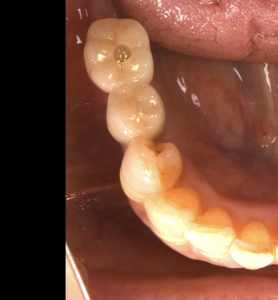

奥歯にインプラントを入れてしっかり噛めるようになった症例

長年奥歯が無い状態で過ごし、またしっかりものを噛めるようになりたいとご来院されました。現在の噛み合わせ、CT、レントゲンで骨の状態や骨質を精査し、2本のインプラントを入れる計画を立てました。術前の計画…